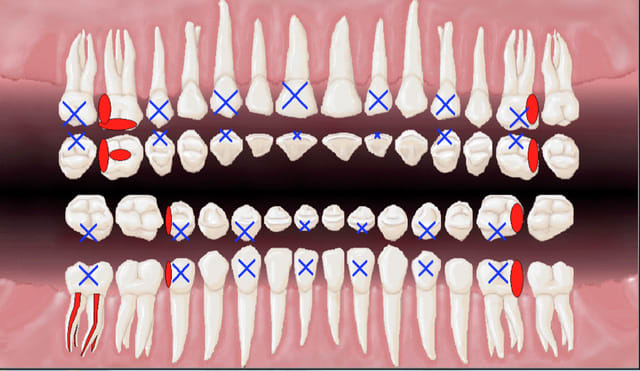

Signes d'appels : néant.

4 rétro coronaires hbqk 443 :

17, 27, 35, 45

diagnostic : caries premier degré sur 14 15 24 25.

Orientation thérapeutique : surveiller.